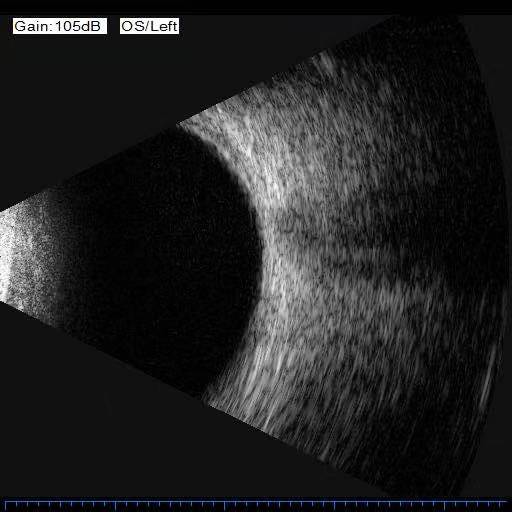

眼科b超检查中发现的眼球内虫幼体

图片尺寸512x512

李大爷右眼b超经过门诊详细检查,李大爷右眼的确也发生了玻璃体积血

今天上午10时,慧慧在医院接受眼科b超检查